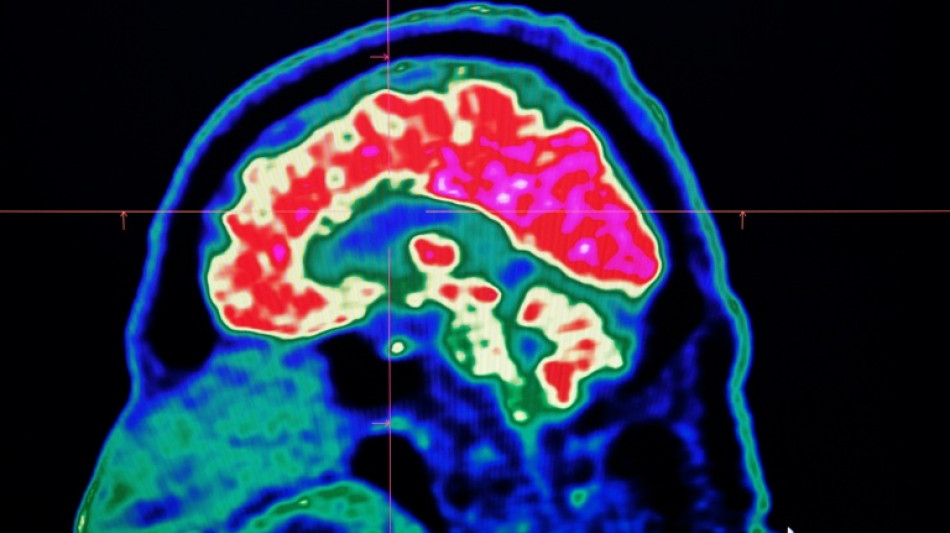

Final report casts doubt on existence of Canada mystery brain illness

Final report casts doubt on existence of Canada mystery brain illness / Photo: © AFP